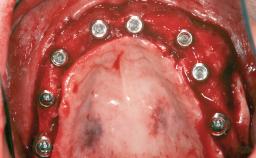

| # of Implants | 4 |

| Type of Implants | One-Piece|Reduced-Diameter |

| Attachment | One-Piece|Reduced-Diameter |